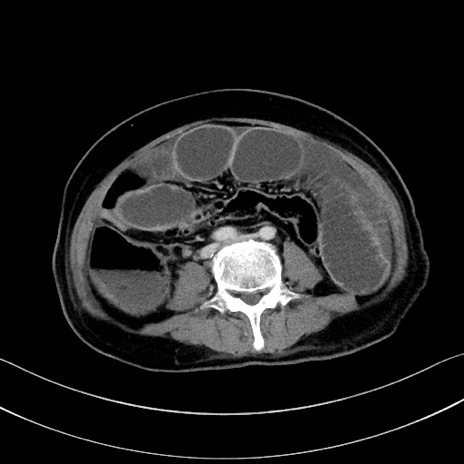

症例28(横断像)

【症例】60歳代男性

【主訴】嘔吐

【現病歴】胃癌にて胃全摘後。食思不振が悪化し、夜中に嘔吐することがある。

【既往歴】胃癌、胃全摘、脾摘、胆摘後

【データ】WBC 5900、CRP 10.56